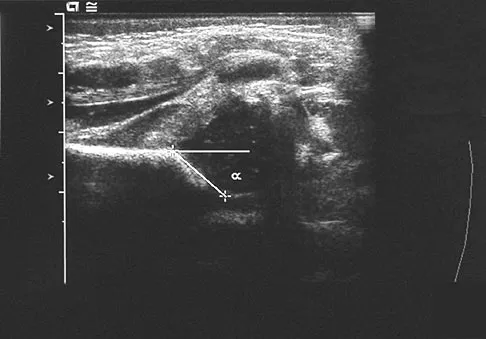

A newborn girl with an isolated unilateral dislocatable hip is placed in a Pavlik harness with the hips flexed 100 degrees and at resting abduction. Figure 23 shows an ultrasound obtained 2 weeks later. What is the next step in management?

Explanation